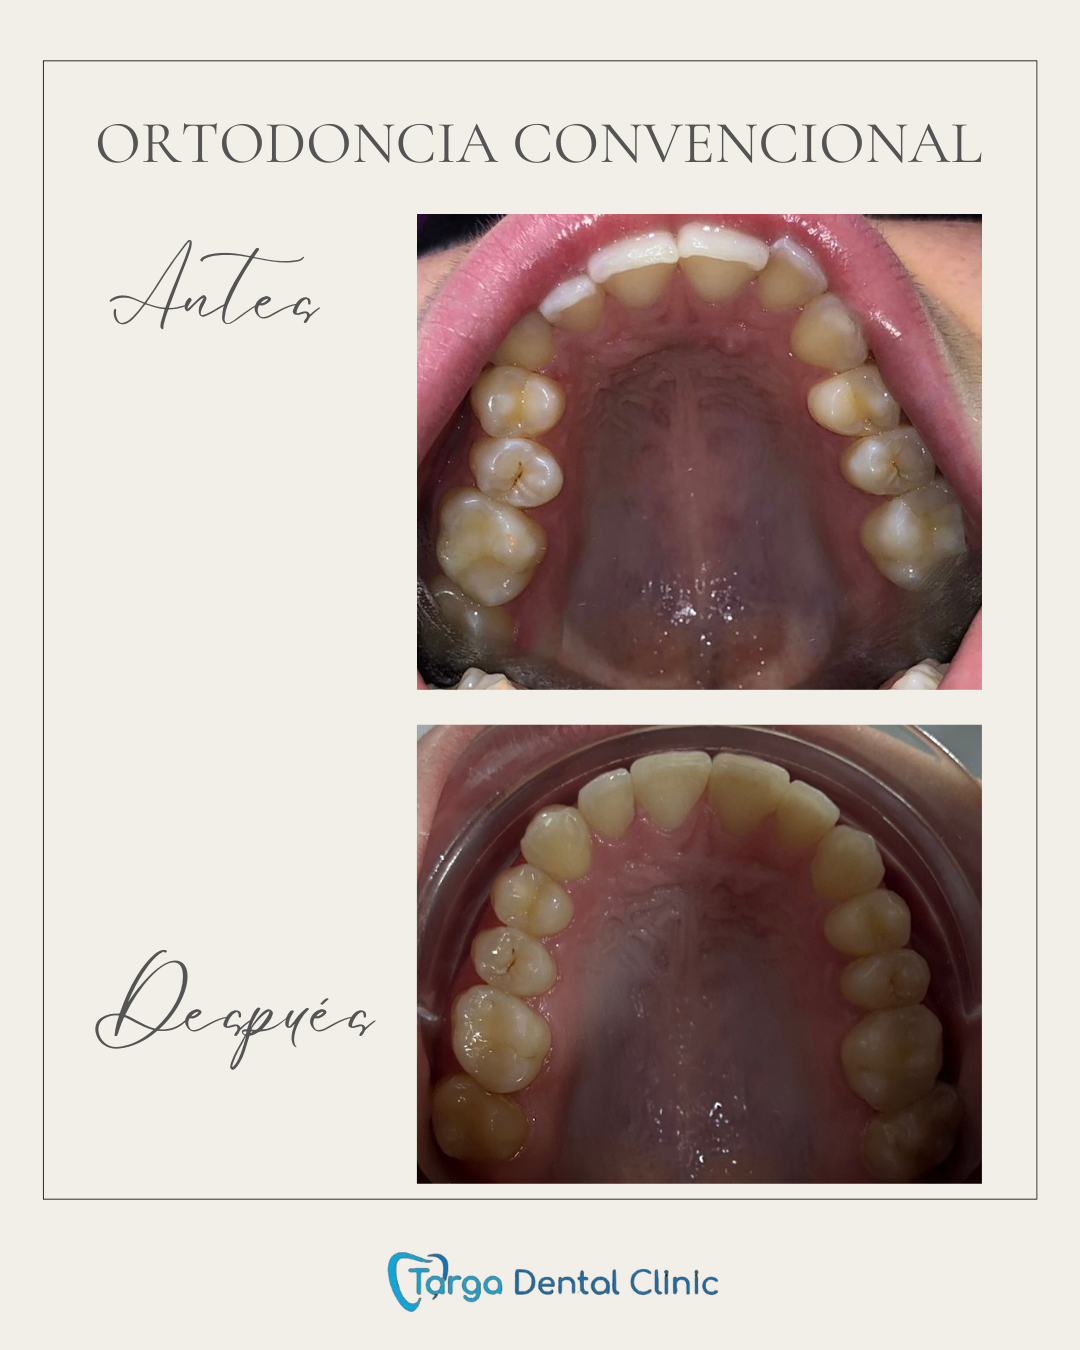

Ortodoncia y Odontopediatría

Ofrecemos tanto ortodoncia invisible con alineadores como ortodoncia fija con brackets.

Evaluamos cada caso y te recomendamos el más adecuado para ti. También ortodoncia para los más pequeños y los pacientes en crecimiento.

Tratamientos realizados en nuestra clínica